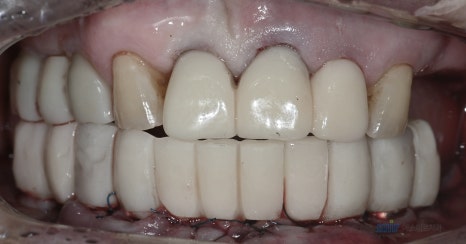

์ด๋ฒ ์์ ์ ํ๋ฃจ์ โ์์ +ํ์ ์ํ๋ํธ ์๋ฆฝ์ด ๋ชจ๋ ์งํ๋์๊ณ ,

๊ฐ์ ๋ , ์์ ๋ณด์ฒ ๋ฌผ๊น์ง ์ธํ ํด๋๋ ธ์ต๋๋ค.

์์ ํ ํ๋ ธ๋ผ๋ง์ ๊ตฌ๊ฐ์ฌ์ง